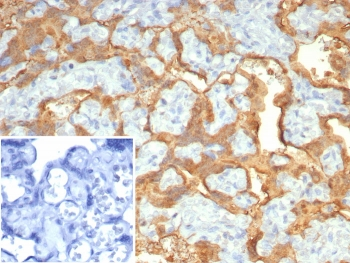

Cathepsin D Antibody

| Catalog Number | orb621663 |

|---|---|

| Category | Antibodies |

| Description | Cathepsin D Antibody |

| Species/Host | Rabbit |

| Clonality | Recombinant |

| Tested applications | FC, ICC, IHC, IP, WB |

| Reactivity | Human, Mouse |

| Antibody Type | Primary Antibody |

| Conjugation | Unconjugated |

| UniProt ID | P07339 |